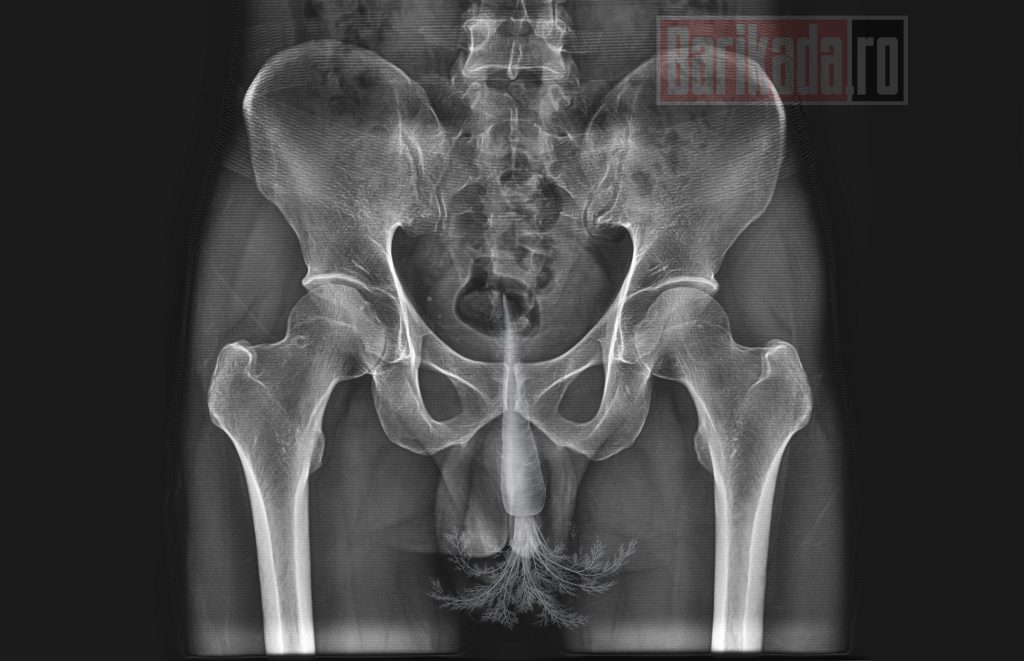

Al doilea caz: morcov blocat rectal

La doar două sau trei zile distanță, un alt pacient, care ar fi pretins despre el că este salariat al unui serviciu de informații, s-a prezentat la aceeași unitate medicală, de această dată cu un morcov blocat în interiorul tractului anal.

Și în acest caz, potrivit informațiilor obținute de reporterii Barikada.ro și Radio Campus, extragerea a necesitat manevre medicale laborioase, pentru a evita leziuni ale mucoasei rectale sau complicații septice.